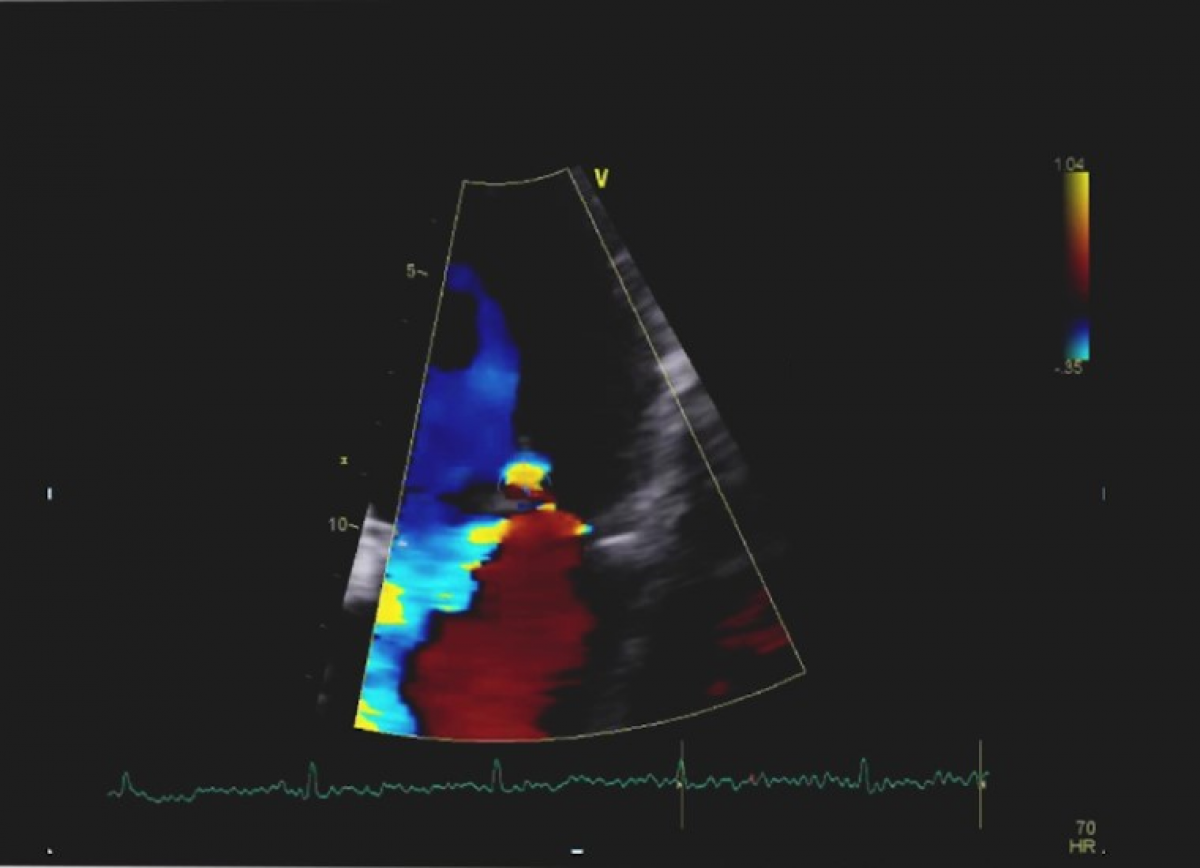

Pacjent z niewydolnością serca NYHA II/III, po przebytym zawale serca

Złożona wada zastawkowa: ciężkie zwężenie, umiarkowana niedomykalność aortalna i ciężka niedomykalność mitralna.

Echokardiografia przezklatkowa

Ocena złożonych wad zastawkowych serca.

Kwalifikacja do leczenia zabiegowego wady aortalnej.